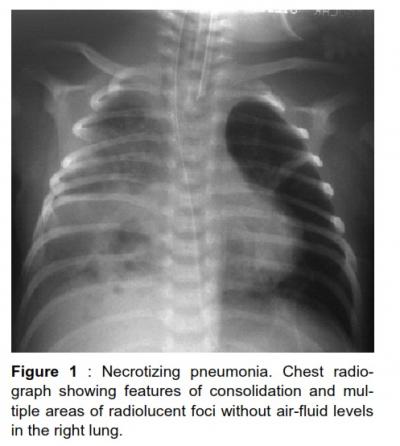

Coagulase negative staphylococcus necrotizing pneumonia

necrotizing pneumonia